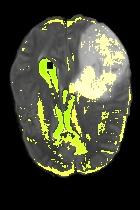

Current unsupervised anomaly localization approaches rely on generative models to learn the distribution of normal images, which is later used to identify potential anomalous regions derived from errors on the reconstructed images. However, a main limitation of nearly all prior literature is the need of employing anomalous images to set a class-specific threshold to locate the anomalies. This limits their usability in realistic scenarios, where only normal data is typically accessible. Despite this major drawback, only a handful of works have addressed this limitation, by integrating supervision on attention maps during training. In this work, we propose a novel formulation that does not require accessing images with abnormalities to define the threshold. Furthermore, and in contrast to very recent work, the proposed constraint is formulated in a more principled manner, leveraging well-known knowledge in constrained optimization. In particular, the equality constraint on the attention maps in prior work is replaced by an inequality constraint, which allows more flexibility. In addition, to address the limitations of penalty-based functions we employ an extension of the popular log-barrier methods to handle the constraint. Comprehensive experiments on the popular BRATS'19 dataset demonstrate that the proposed approach substantially outperforms relevant literature, establishing new state-of-the-art results for unsupervised lesion segmentation.